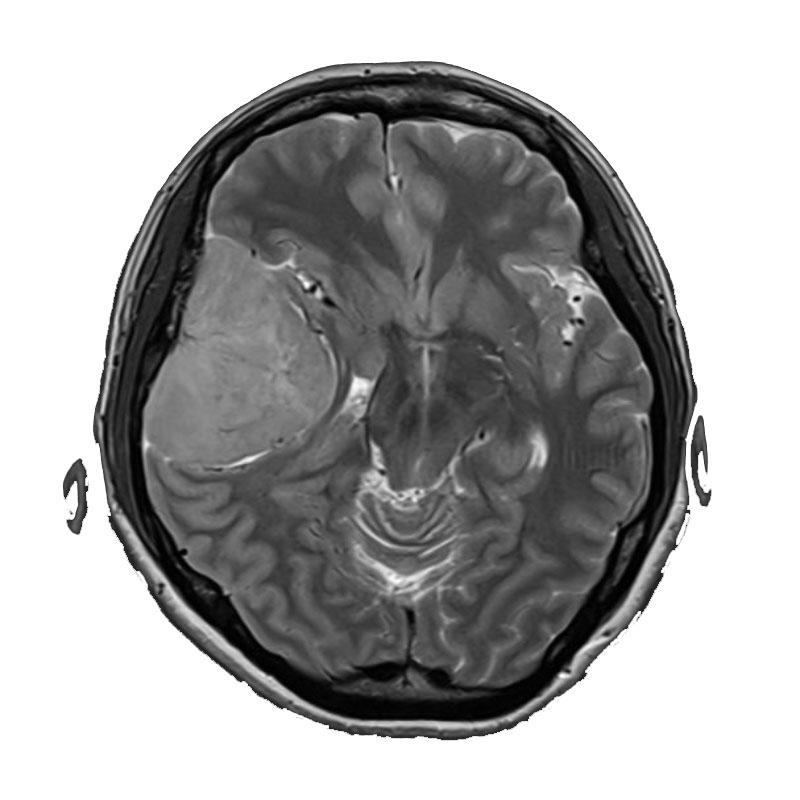

右側頭葉脳腫瘍

摘出術

南田/野本/佐伯